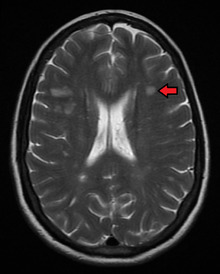

The name multiple sclerosis refers to the scars (sclerae – better known as plaques or lesions) that form in the nervous system. These lesions most commonly affect the white matter in the optic nerve, brain stem, basal ganglia, and spinal cord, or white matter tracts close to the lateral ventricles.[5] The function of white matter cells is to carry signals between grey matter areas, where the processing is done, and the rest of the body. The peripheral nervous system is rarely involved.[8]

To be specific, MS involves the loss of oligodendrocytes, the cells responsible for creating and maintaining a fatty layer—known as the myelin sheath—which helps the neurons carry electrical signals (action potentials).[5] This results in a thinning or complete loss of myelin and, as the disease advances, the breakdown of the axons of neurons. When the myelin is lost, a neuron can no longer effectively conduct electrical signals.[8] A repair process, called remyelination, takes place in early phases of the disease, but the oligodendrocytes are unable to completely rebuild the cell's myelin sheath.[49] Repeated attacks lead to successively less effective remyelinations, until a scar-like plaque is built up around the damaged axons.[49] These scars are the origin of the symptoms and during an attack magnetic resonance imaging (MRI) often shows more than ten new plaques.[5] This could indicate that there are a number of lesions below which the brain is capable of repairing itself without producing noticeable consequences.[5] Another process involved in the creation of lesions is an abnormal increase in the number of astrocytes due to the destruction of nearby neurons.[5] A number of lesion patterns have been described.[50]

Clinical data alone may be sufficient for a diagnosis of MS if an individual has had separate episodes of neurological symptoms characteristic of the disease.[54] In those who seek medical attention after only one attack, other testing is needed for the diagnosis. The most commonly used diagnostic tools are neuroimaging, analysis of cerebrospinal fluid and evoked potentials. Magnetic resonance imaging of the brain and spine may show areas of demyelination (lesions or plaques). Gadolinium can be administered intravenously as a contrast agent to highlight active plaques and, by elimination, demonstrate the existence of historical lesions not associated with symptoms at the moment of the evaluation.[54][55] Testing of cerebrospinal fluid obtained from a lumbar puncture can provide evidence of chronic inflammation in the central nervous system. The cerebrospinal fluid is tested for oligoclonal bands of IgG on electrophoresis, which are inflammation markers found in 75–85% of people with MS.[54][56] The nervous system in MS may respond less actively to stimulation of the optic nerve and sensory nerves due to demyelination of such pathways. These brain responses can be examined using visual- and sensory-evoked potentials.[57]